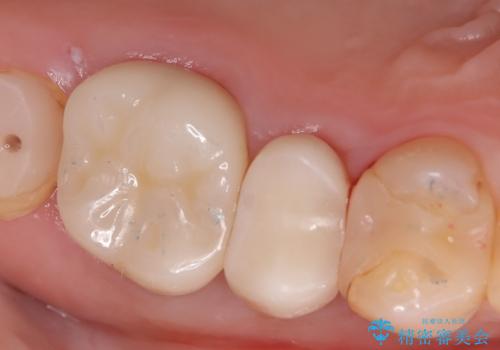

「右上4番目と5番目の間にフロスを通すといつも出血し、たまに臭いもする」という主訴で来院されました。

右上4番に歯冠色インレーが入っており、遠心側室エリアのマージン不適を認め、そこに汚れが溜まりやすい状態となっていました。